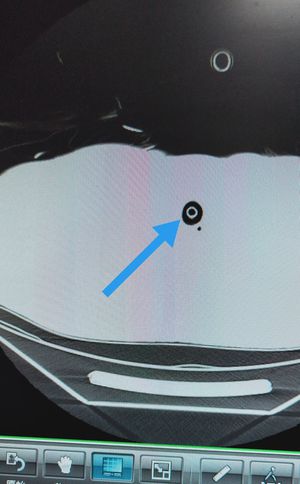

This is a transverse chest CT ,lung window ,just prior to begining of the lung itself , the arrow is pointing to sth specific which is easily unnoticed(like a needle in a haystack) , so can you find it?

Nice try but no , ribs don't appear at centre of a transverse ct ,they are peripheral.

Hint guys: centre of the chest ,just prior to begin of lungs on transverse CT, regular circle in shape and black(air) inside, what are we talking about now? 🤔